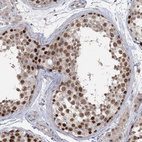

Immunohistochemistry analysis in human testis and cerebral cortex tissues using HPA037503 antibody. Corresponding UIMC1 RNA-seq data are presented for the same tissues.